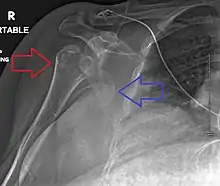

Lightbulb sign indicative of posterior shoulder dislocation shown on the left. On the right, the same shoulder after reduction.

Axillary view of the left shoulder showing a posterior dislocation